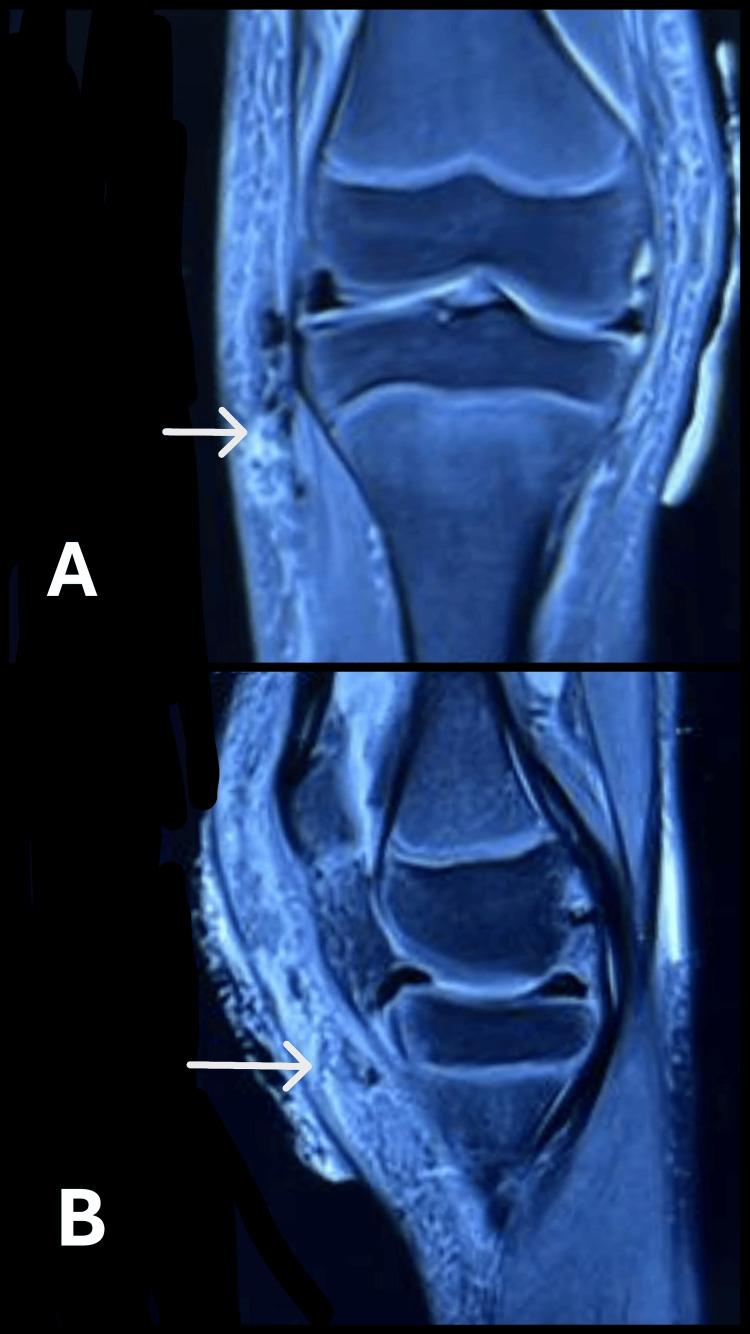

Tumoral calcinosis is a debilitating complication of juvenile dermatomyositis (JDM) that results from dystrophic calcification in inflamed soft tissues. Although often asymptomatic, it can occasionally be complicated by secondary infections, requiring both medical and surgical interventions. Here, we report a rare case of tumoral calcinosis with superadded infection in a child with JDM, along with a brief pathophysiological and therapeutic overview. An 11-year-old girl with a known history of JDM presented with fever and localized pain in the right knee. Examination revealed local warmth, mild joint restriction, and no other systemic signs. Imaging demonstrated periarticular soft tissue calcifications without osseous involvement. MRI and CT scans confirmed lobulated, calcified soft tissue masses with surrounding edema. The patient underwent surgical incision, drainage, and excision of accessible calcified nodules. Histopathology confirmed tumoral calcinosis with associated inflammation. Postoperative rehabilitation began two weeks after surgery, with favorable functional recovery. Calcinosis in JDM develops through chronic inflammation, metabolic imbalance, and impaired calcium clearance due to dysfunctional macrophages. Contributing factors include genetic susceptibility, immune complex deposition, and mitochondrial injury. Imaging, particularly MRI and CT, is critical for diagnosis and surgical planning. Management requires a multidisciplinary approach, including phosphate restriction, chelation therapy, immunosuppressive agents, and selective surgical excision. Emerging options such as antioxidants, including N-acetylcysteine, have shown promise in slowing disease progression. This case underscores the importance of early recognition and targeted therapy for tumoral calcinosis in JDM. Prompt, coordinated intervention can help prevent irreversible joint damage and improve the quality of life in affected children.